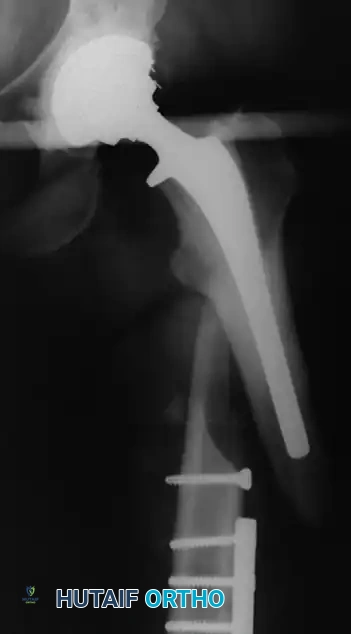

Associated Surgical & Radiographic Imaging